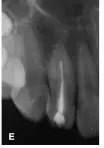

25個(gè)月后復(fù)診:X線片顯示i根尖區(qū)暗影消失,主根管根尖基本閉合,根尖愈合(圖1E)。復(fù)診時(shí)發(fā)現(xiàn)同為牙中牙的2牙體稍變色,牙髓熱測試無反應(yīng),診斷為2牙髓壞死,2開髓后可探及內(nèi)陷根管的根尖止點(diǎn),測量工作長度為22mm,25~30號(hào)擴(kuò)挫后Vitapex充填內(nèi)陷根管,磷酸鋅水門汀封洞(圖1F),調(diào)牙合消除2咬合干擾,囑以后每隔半年復(fù)診1次,適時(shí)行內(nèi)陷根管的根管治療。

圖1E:治療后25個(gè)月4主根管根尖閉合;F::2 Vitapex充填內(nèi)陷根管